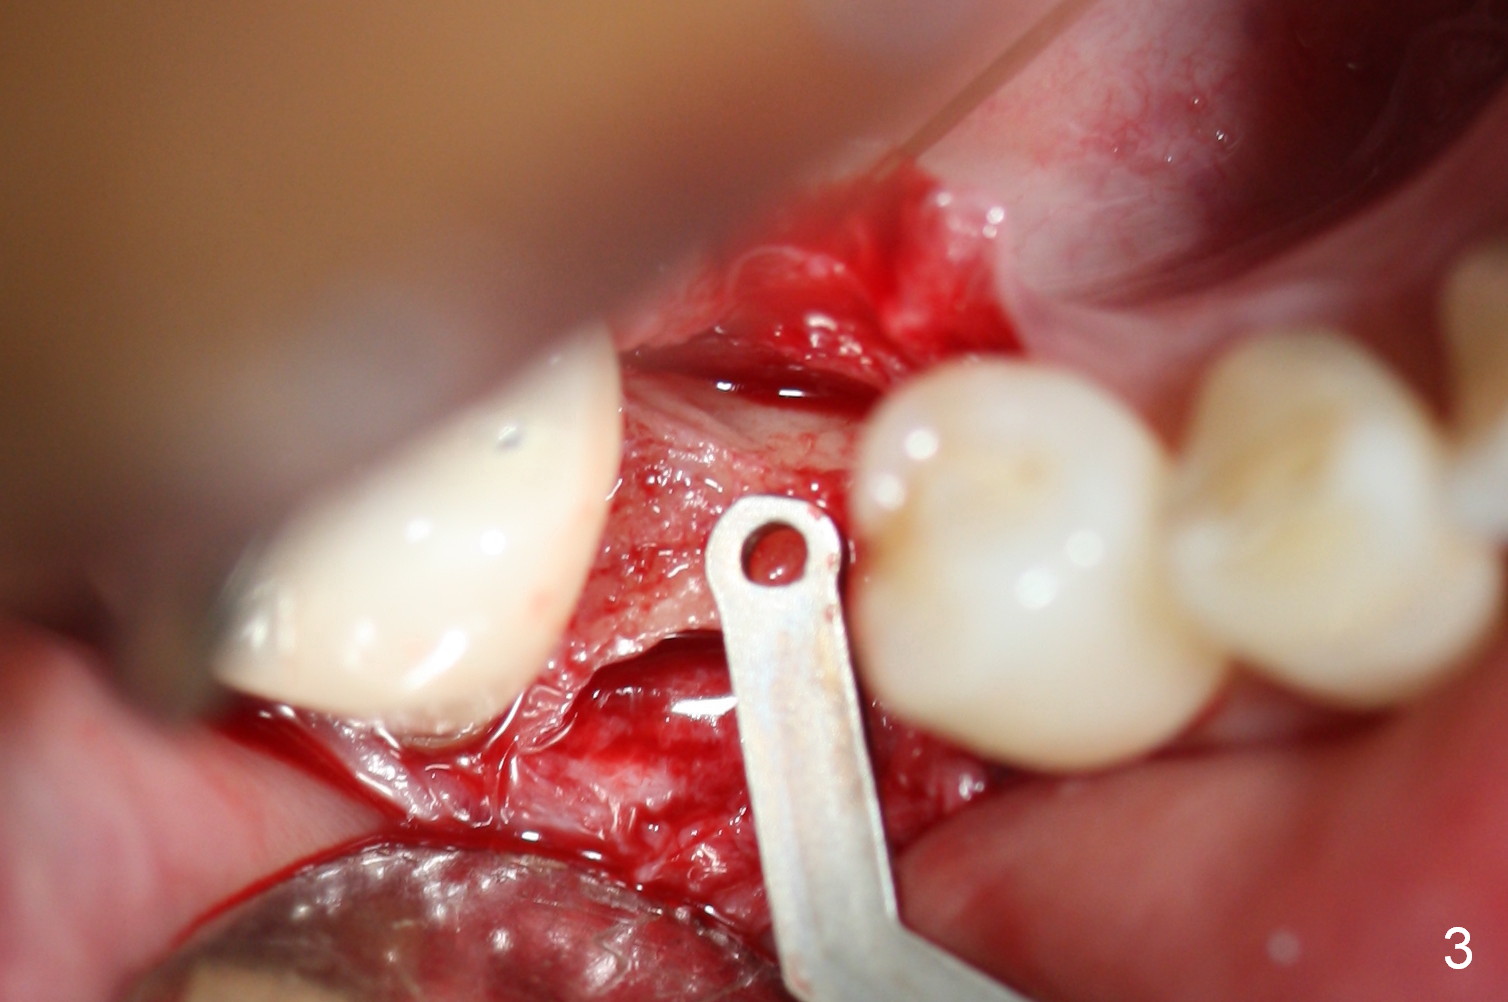

Preop photo shows the distal inclination of the tooth #28 (Fig.1).  The distal surface of the latter is reduced before incision for implant placement at #29 (Fig.2).  The buccolingual width is approximately 4 mm, as compared to 3 mm implant positioner (Fig.3).  After 1.2x10 mm osteotomy (Fig.5), the mesiodistal cortical bone is removed with a small high-speed fissural bur (Fig.4).  When a 2.5x12(2) mm 1-piece implant is placed (Fig.6), there is no buccal (Fig.7) or lingual plate perforation.  There is no postop paresthesia.  There is mild bone loss distal 4 months postop (Fig.8 *).  Take photos before and after permanent crown cementation to show increase in ridge width after bone graft and improvement in gingival health after provisional modification.  Take PA and/or BW post cementation to show that the distal bone resorption (Fig.8 *) is partially due to angulation.  No continuous bone loss 15 months post cementation (Fig.9).  There is mild bone resorption mesially 2 years 3 months post cementation (Fig.10).  The soft and hard tissues remain healthy 4 years 3 months post cementation (Fig.11,12).